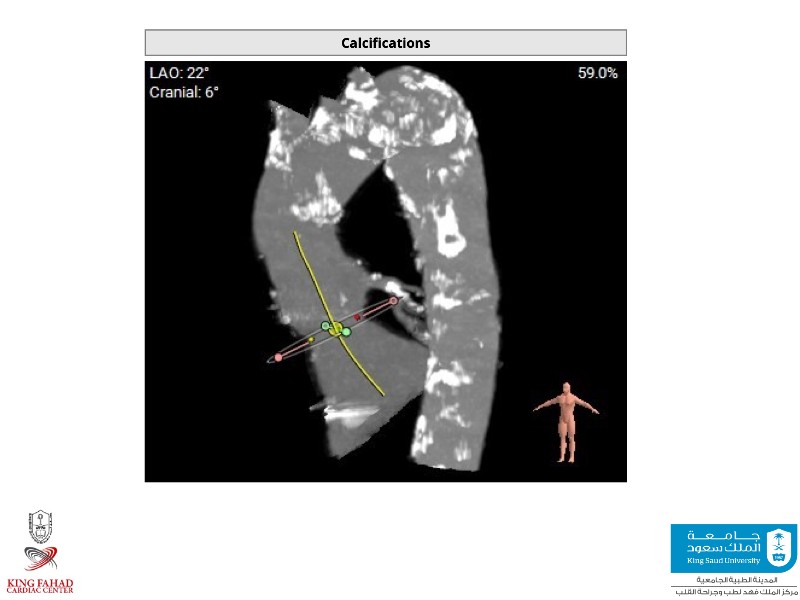

This session helps you anticipate and address complex scenarios such as mitral valve-in-valve, TAV-in-SAV, and valve-in-valve-in-valve procedures. Learn from expert case discussions that explore procedural strategies, technical challenges, and best practices to optimize outcomes in redo structural heart interventions.

- To anticipate and manage second valve scenarios with SAPIEN 3 Ultra RESILIA, including mitral valve-in-valve, TAV-in-SAV, and TAV-in-TAV

- To understand procedural strategies and challenges in complex redo scenarios using SAPIEN 3 Ultra RESILIA